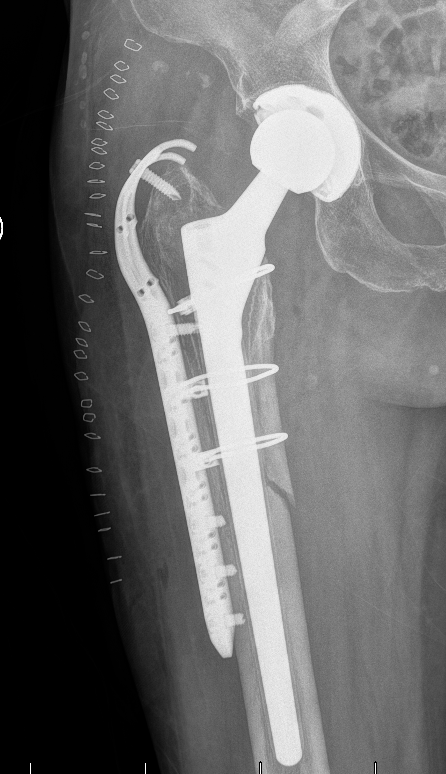

杨小海主任团队为患者实施髋关节翻修术